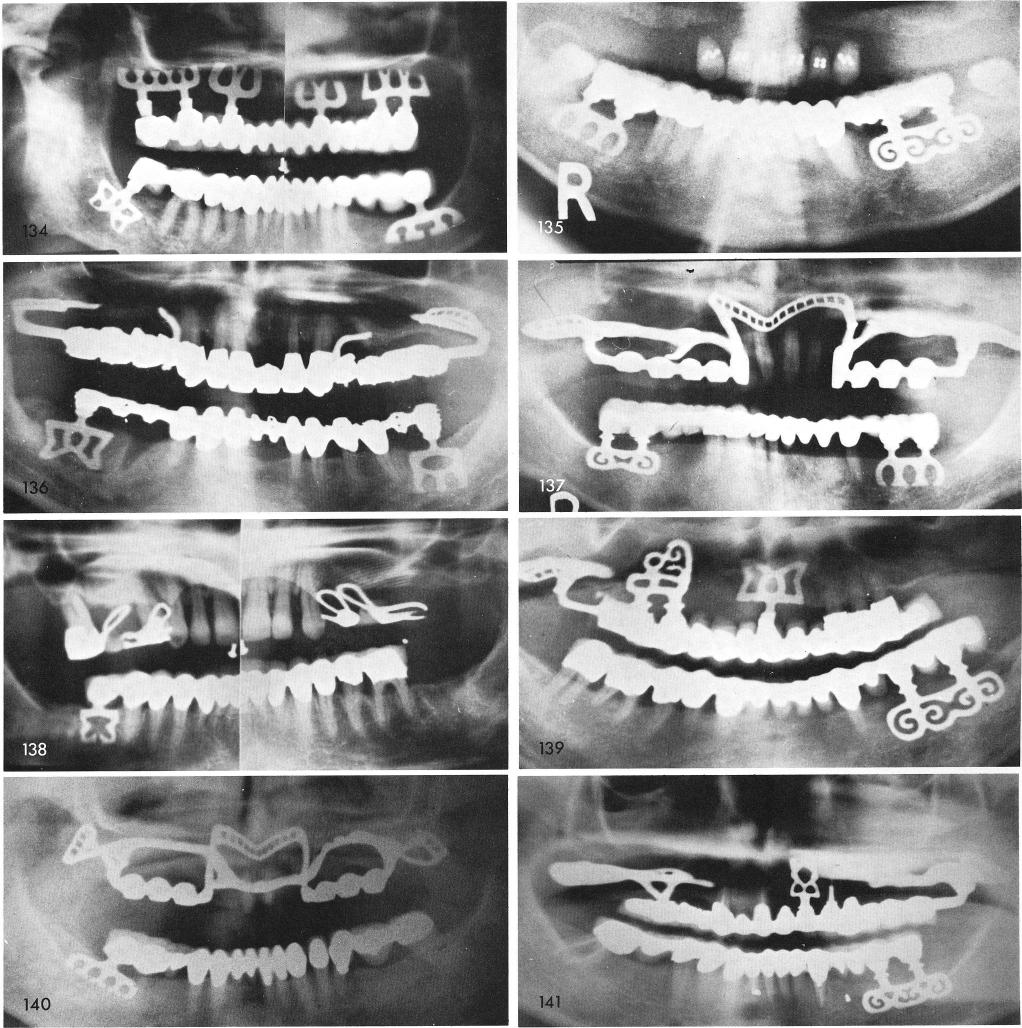

Mandibular Implants (published 1977)   Dr. Leonard I. Linkow